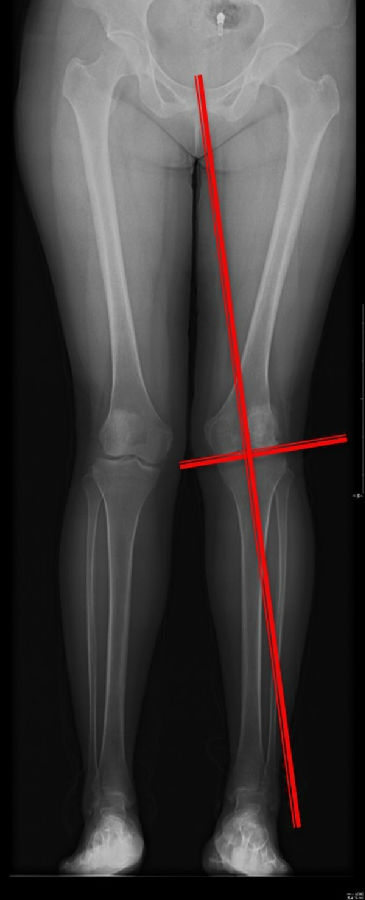

画下肢机械轴,股骨头中心链接踝关节中心判断患者为内翻畸形还是外翻畸形。此患者为外翻畸形。

步骤二:判断畸形部位